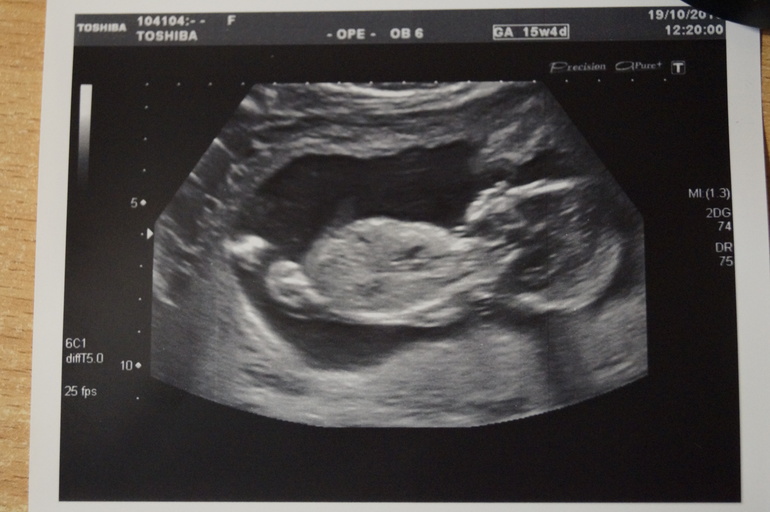

Результаты: УЗИ, КТГ, доплера, скринингаСрок 15-16 недель. Ну не могу я ждать до 22-24 недель. Очень хотелось познакомить малыша и папу. Да и самой убедиться, что с ребЯтёнком всё в порядке. В субботу 19 октября повела папу на узи.

Всё у нас хорошо. Всё в норме. Всё по срокам. И это не может не радовать!!!! Определили девочку. Муж даже сказал, что давно уже знает как малышку назовём. Спрашиваю:"И как же?" Сначала он не хотел говорить. Но ведь я, разговаривая с дочкой должна по имени её называть!!!! Сдался. Говорит:"Виктория! Наша победа!" Я согласилась. Тоже думала, что если девочка, то будет либо Викторией, либо Вероникой. Хотя была готова и к мальчику. Главное, чтоб здоровый, счастливый и любимый ребёнок. И вот наша Виктория.... Виктория Артёмовна с носиком, ротиком, ушками, ножками и ручонками. Даже помахала папе ручкой.